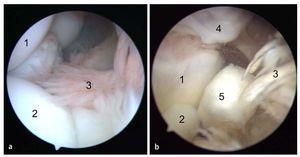

Fig. 8 a) Mediante un artroscopio estándar (ángulo visual de 30º) es posible visualizar el compartimento anterior. Primero se observa el húmero distal (1), la cabeza del radio (2) y el tejido sinovial (3). b) A continuación se desplaza el artroscopio más hacia el interior del compartimento anterior. Aquí se pueden observar la tróclea humeral (1), el proceso coronoides (2) y el tejido sinovial (3). Con frecuencia se observan osteofitos (4) en la zona del húmero anterior, así como cuerpos articulares libres (5).